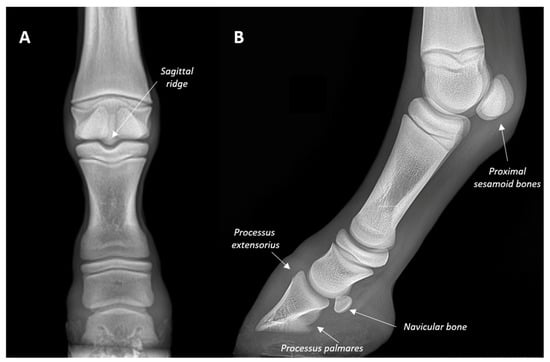

- Butler, J.A.; Colles, C.M.; Dyson, S.J.; Kold, S.E.; Poulos, P.W. Clinical Radiology of the Horse, 3rd ed.; John Wiley & Sons: Chichester, UK, 2017; pp. 55–148. [Google Scholar]

- Collins, S.N.; Dyson, S.J.; Murray, R.C. Radiological anatomy of the donkey foot: Objective characterization of the normal and laminitic donkey foot. Equine Vet. J. 2011, 43, 478–486. [Google Scholar] [CrossRef]

- Nocera, I.; Aliboni, B.; Puccinelli, C.; Pietrini, G.; Sgorbini, M.; Citi, S.; Ricardi, G. Radiographic parameters of the digit in a cohort population of Amiata donkeys. Open Vet. J. 2020, 10, 354–362. [Google Scholar] [CrossRef] [PubMed]